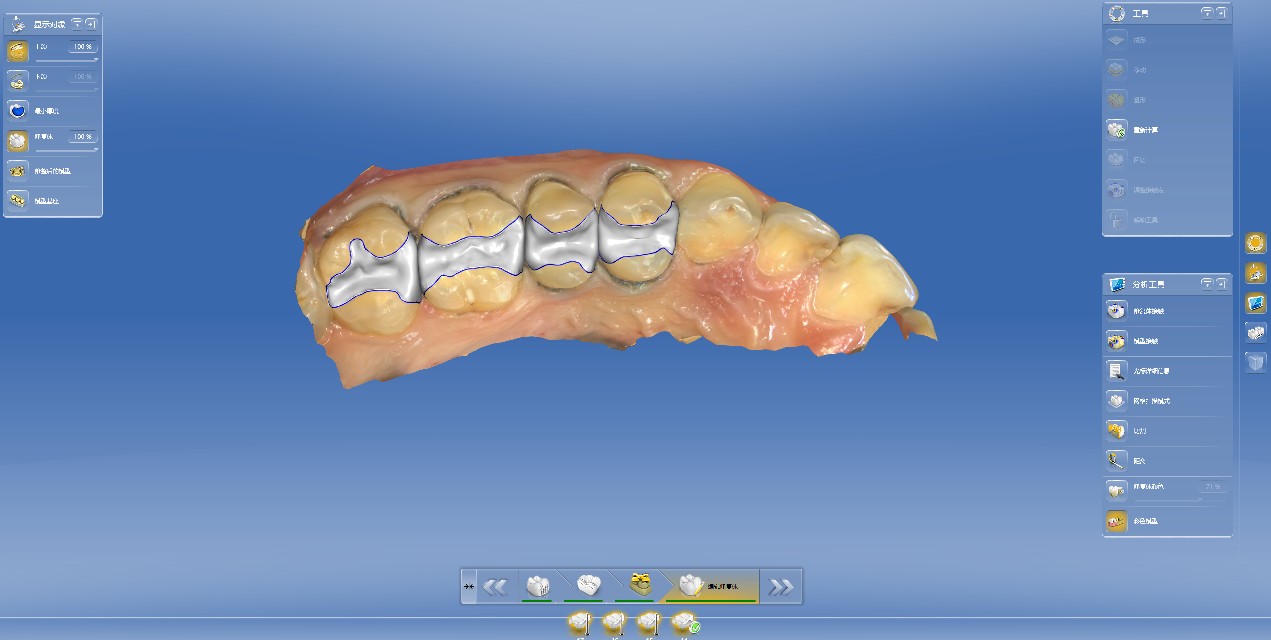

门诊经常遇到常年把碳酸饮料当水喝的患者,严重损伤了牙齿的健康,检查发现牙齿脱矿.龋坏特别严重,特别是邻面龋坏,治疗也非常麻烦,很多情况下,简单的补牙都解决不了长久性问题,想要经久耐用,可以选择嵌体,高嵌体,全瓷牙冠修复,更重要是杜绝不良嗜好;有图有真相!我们采用德国西诺德瓷睿刻即刻修复系统,等待1小时,完成当日修复。